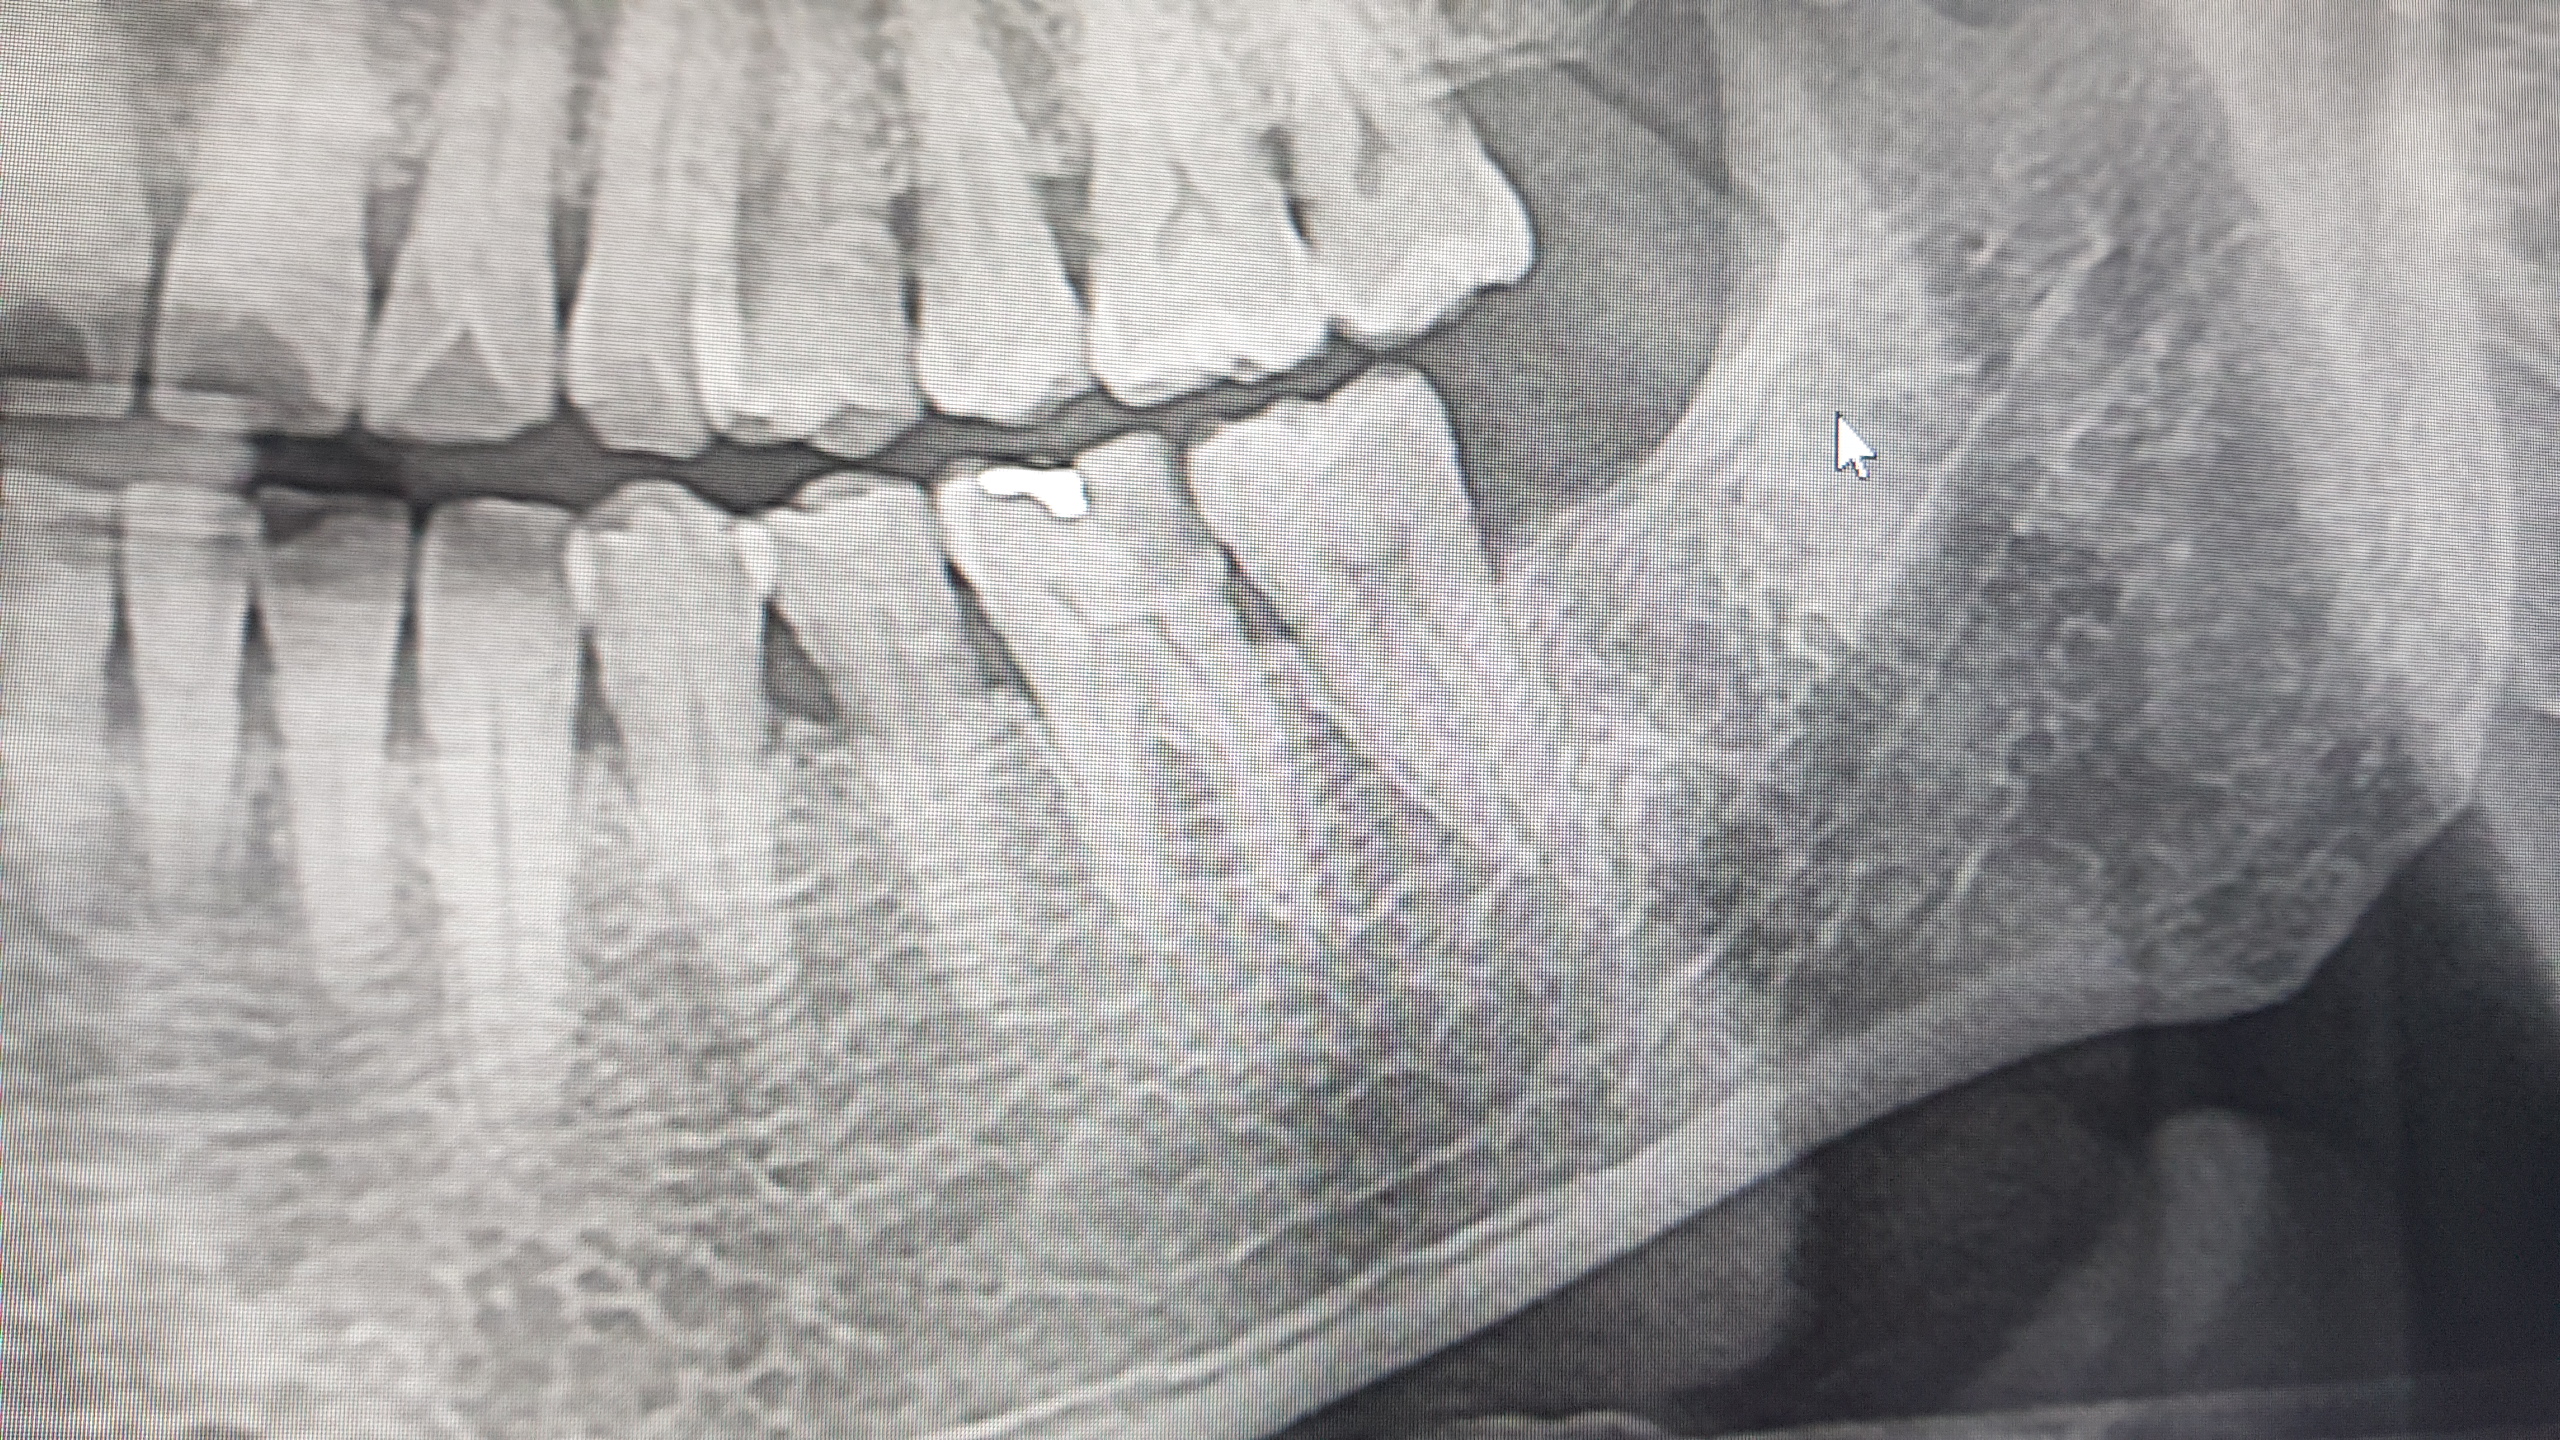

일단 ..또다시 엑스레이를 찍고..

여기서도..신경 치료를 해야한다고 한다.